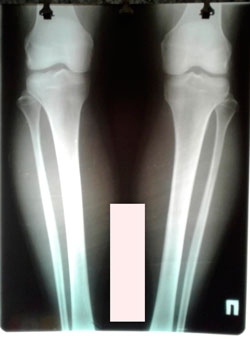

Исходник 33 года.

Дата операции - 09.10.2020

image-31-10-20-02-18-1.jpg

image-31-10-20-02-18-7.jpg